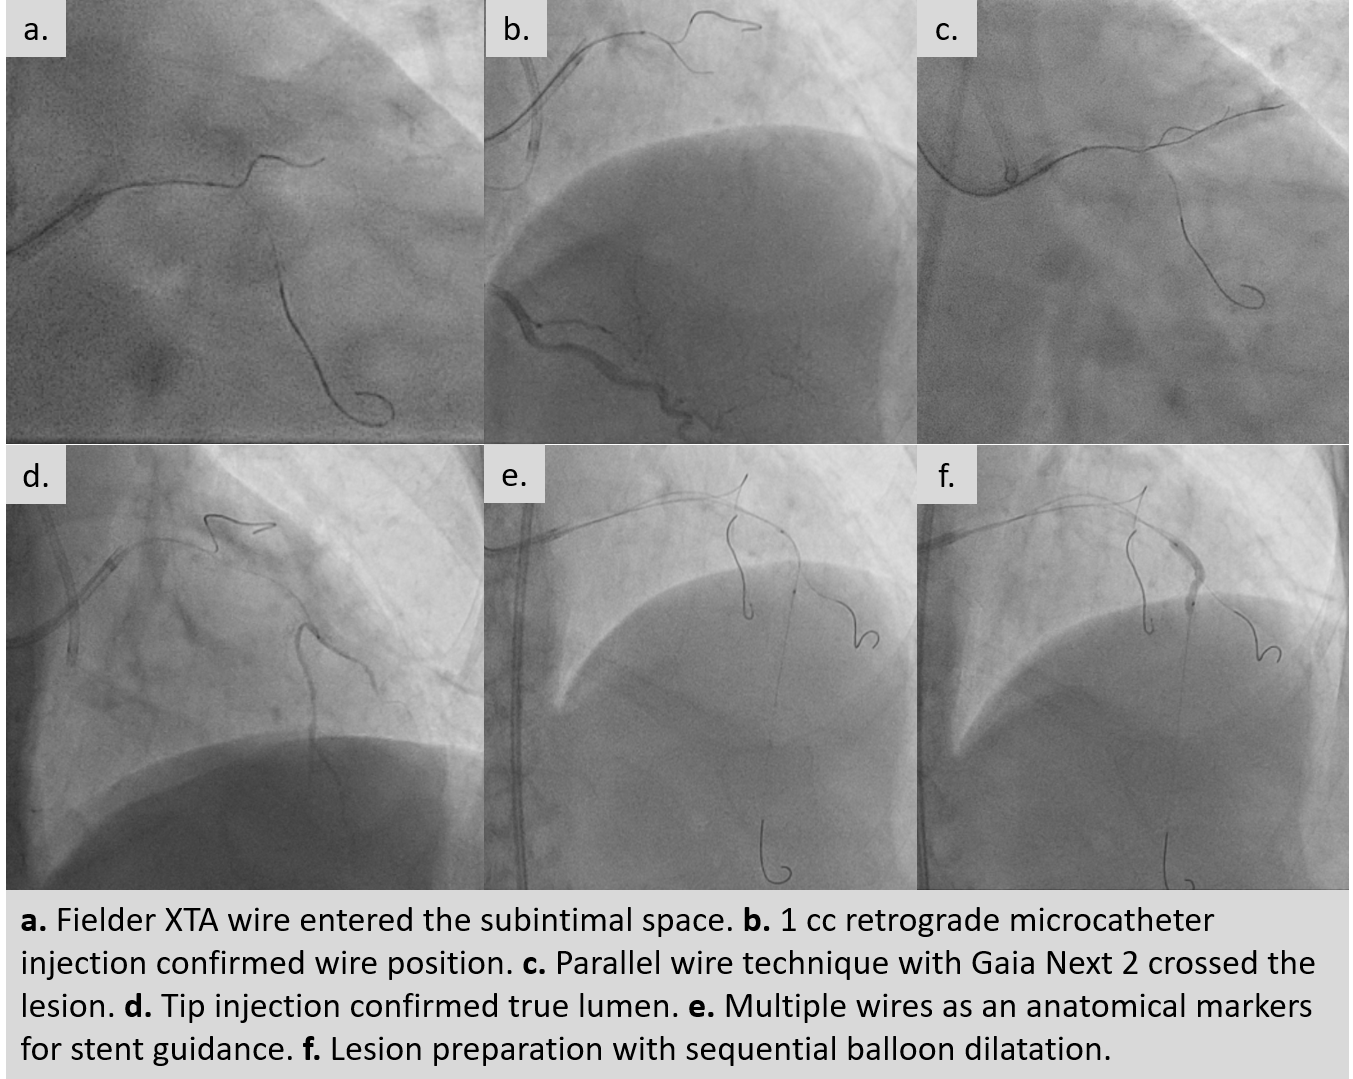

An ultra low contrast PCI of the LAD was performed using dual puncture with EBU 3.5/7F and JR 3.5/6F catheters via radial and femoral access. Saline was used for engagement, with contrast restricted to microcatheter injections of 1 cc each as a sparing strategy. Antegrade proximal cap puncture with Finecross and Fielder XTA tracked subintimally, and a parallel wire technique with Gaia Next 2 successfully crossed the lesion, confirmed by retrograde injection. Lesion preparation was achieved with a semicompliant balloon (2.5 ¡¿ 15 mm) from mid to proximal LAD and a cutting balloon (2.75 ¡¿ 18 mm) from mid to ostium LAD. IVUS pullback revealed a long diffuse lesion with proximal and ostial calcification, showing calcium cracks after preparation. MLA at the ostium LAD was 2.5 mm©÷, distal reference diameter 2.8 mm, and LM diameter 4.5 mm. Stent deployment was guided by multiple wires as anatomical landmarks without contrast. A DES (3.5 ¡¿ 28 mm) was implanted from distal LM crossover to proximal LAD, followed by POT with a 4.0 ¡¿ 9 mm NC balloon. A second DES (2.75 ¡¿ 28 mm) was placed in proximal to mid LAD overlapping the first, with post-dilation using a 3.0 ¡¿ 15 mm NC balloon. IVUS confirmed well-expanded, well-apposed stents without edge dissection. Final MSA was 12 mm©÷ in LM, 10.8 mm©÷ in ostium LAD, and 6.3 mm©÷ in mid LAD. Final angiography with diluted contrast demonstrated TIMI 3 flow, with total contrast use limited to 12 cc.